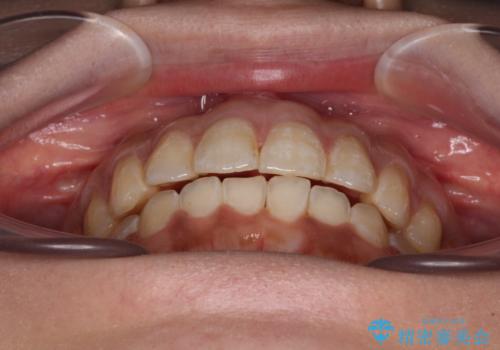

舌突出癖改善のためのトレーニングを行いながら、インビザラインにて矯正治療を行うこととしました。

舌のトレーニングをしっかりと行っていただき、上下前歯をしっかりと接触させることができました。

咬合力が強いため、治療途中に奥歯が咬み合わない期間が続きましたが、上下の奥歯でゴムかけを行っていただき、違和感なく咬み合うように仕上げることができました。